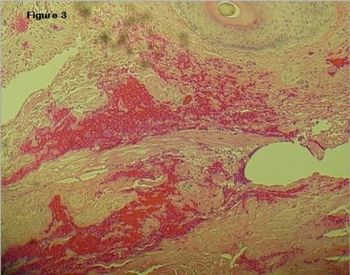

A 32-year-old man with no significant medical history presents with multiple scrotal lesions that he claims have been present for 2 years. They are non-tender and he reports no overt symptoms. The full case, here.